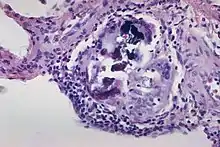

In this image there are multiple Schaumann bodies with crystalline inclusions.[1] Schaumann bodies are calcium and protein inclusions inside of Langhans giant cells as part of a granuloma.[2]

1. USA, Yale Rosen from (2011-08-04), The crystalline inclusions that may be found within the giant cells in sarcoidosis and other granulomatous disorders consist mainly of calcium oxalate and well as some calcium cargbonate. In this image there are multiple Schaumann bodies closely associated with crystalline inclusions. In many cases the crystals appear to serve as a nidus around which Schaumann bodies are formed. H&E stain., retrieved 2021-12-10